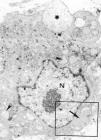

El estudio ultraestructural puso de relieve la presencia en la dermis de abundantes fibroblastos, dispuestos entre gruesos paquetes de fibras de colágeno y amplias formaciones redondeadas de material mucoide (fig. 1). Los fibroblastos mostraban las características de células sumamente activas. Presentaban un núcleo con cromatina laxa y nucléolo evidente, con una membrana doble que mostraba varios poros nucleares (figs. 2 y 3). En el citoplasma destacaba un retículo endoplásmico rugoso prominente, muchas de cuyas cisternas aparecían dilatadas, por lo que le conferían un aspecto vesicular. Así mismo, la dotación mitocondrial era importante, junto a las vesículas con un contenido de baja electrodensidad. En algunos de los fibroblastos se apreciaba cómo liberaban las vesículas de aspecto mucinoso al espacio intercelular (fig. 2). Completaba la elevada actividad de estas células la presencia, en algunas de ellas, de fibras de colágena recién polimerizadas, liberándose mediante la emisión de prolongaciones citoplasmáticas, a modo de pseudópodos (fig. 3) y que una vez en el espacio intercelular, se acoplaban formando gruesos paquetes de colágeno.

Fig. 2.--Fibroblasto cortado transversalmente, muestra la riqueza de organelas características de una célula en gran actividad de síntesis. N: núcleo con nucléolo evidente. *: vesícula de sustancia mucoide. Punta de flecha: cisternas dilatadas de retículo endoplásmico rugoso. Flecha: paquete de fibras de colágena. Recuadro: fig. 3. (Aumentos, x12.500.)